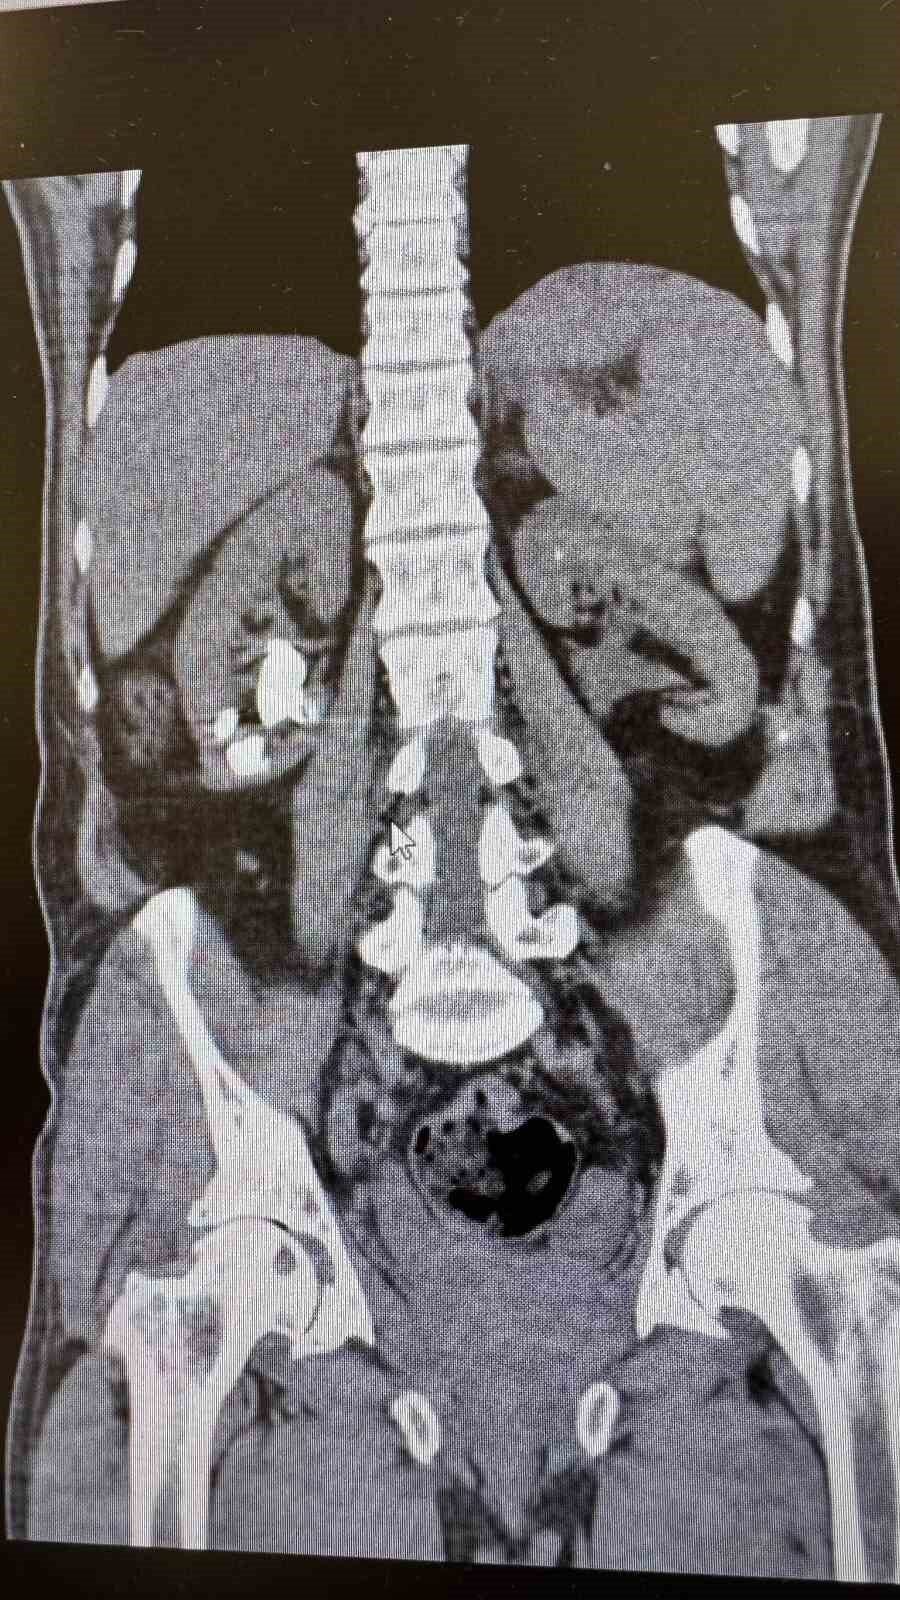

Antalya Gazipaşa Devlet Hastanesi’nde gerçekleştirilen iki başarılı operasyonla 62 yaşındaki hasta böbrek taşlarından tamamen kurtuldu.

Üroloji Uzmanı Op. Dr. İlker Fatih Şahiner ve ekibince kapalı yöntemle (PNL) yapılan ameliyatlarda hastanın her iki böbreğindeki tekrarlayan sistin taşları temizlendi. Hastanın daha önce 10’un üzerinde böbrek taşı ameliyatı geçirdiği öğrenildi. Mayıs ayında yapılan ilk operasyonla sol böbrekteki taşlar alınırken, geçtiğimiz salı günü gerçekleştirilen ikinci operasyonla sağ böbrekteki taşlar da temizlendi.

Operasyonları gerçekleştiren Üroloji Uzmanı Op. Dr. İlker Fatih Şahiner, “Hastamızın her iki böbreğinde de tekrarlayan sistin taşları mevcuttu. Mayıs ayında sol böbreğine PNL yaparak taşsızlık sağlamıştık. Dün de sağ böbreğine PNL ameliyatını yaparak taşsızlık sağladık. Hastamızın genel durumu iyi, tedavisi servisimizde devam ediyor” dedi.

Başarılı operasyonların ardından hastanın yıllardır süren böbrek taşı sorunundan tamamen kurtulduğu bildirildi.